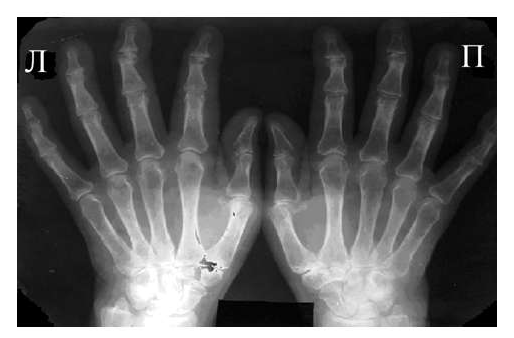

Рис. 3 Сочетание ревматоидного артрита и остеоартроза

Большинство ошибок встречаются при начальных стадиях, особенно при начале РА в пожилом возрасте и сочетании его с остеоартрозом (см. рис. 3). В этом случае для подтверждения диагноза РА и предупреждению случаев его гипердиагностики служит выявление симметричных эрозий в типичных для ревматоидного артрита суставах (запястья, плюснефаланговые, пястно-фаланговые).

Необходимо также помнить, что, как правило, при РА эрозии не предшествуют околосуставному остеопорозу, кистам и сужению суставных щелей. Имеет место последовательность развития стадий РА (см. рис. 4), в отличие от эрозивных артритов другого генеза (псориатического, серонегативного)